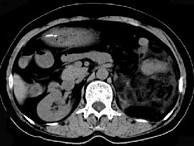

问题 女,64岁,左侧腰部胀痛,行CT扫描,下列说法正确的是()

选项 A.左肾区可见一巨大的占位性病灶,境界较清楚,胰腺尾部受压向前推移 B.该病灶密度不均匀,其内可见脂肪密度影,且呈不均匀强化 C.考虑为左肾来源的血管平滑肌脂肪瘤 D.考虑为左侧肾上腺来源的髓样脂肪瘤 E.考虑为腹膜后来源的脂肪肉瘤

答案 ABC